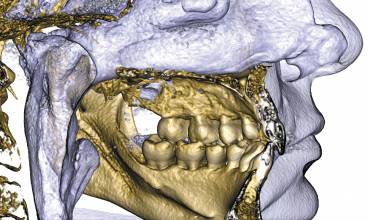

Мощный и настраиваемый фильтр компенсации артефактов. Даже после снимка! Можно удалить темные и светлые полосы, связанные с присутствием металла, для более эффективной дифференциации тканей (кость/зуб/металл). Изображение может быть изменено уже после снимка, с адаптируемыми уровнями фильтров, в соответствии с предполагаемым объемом информации и необходимостью уменьшения артефактов. |